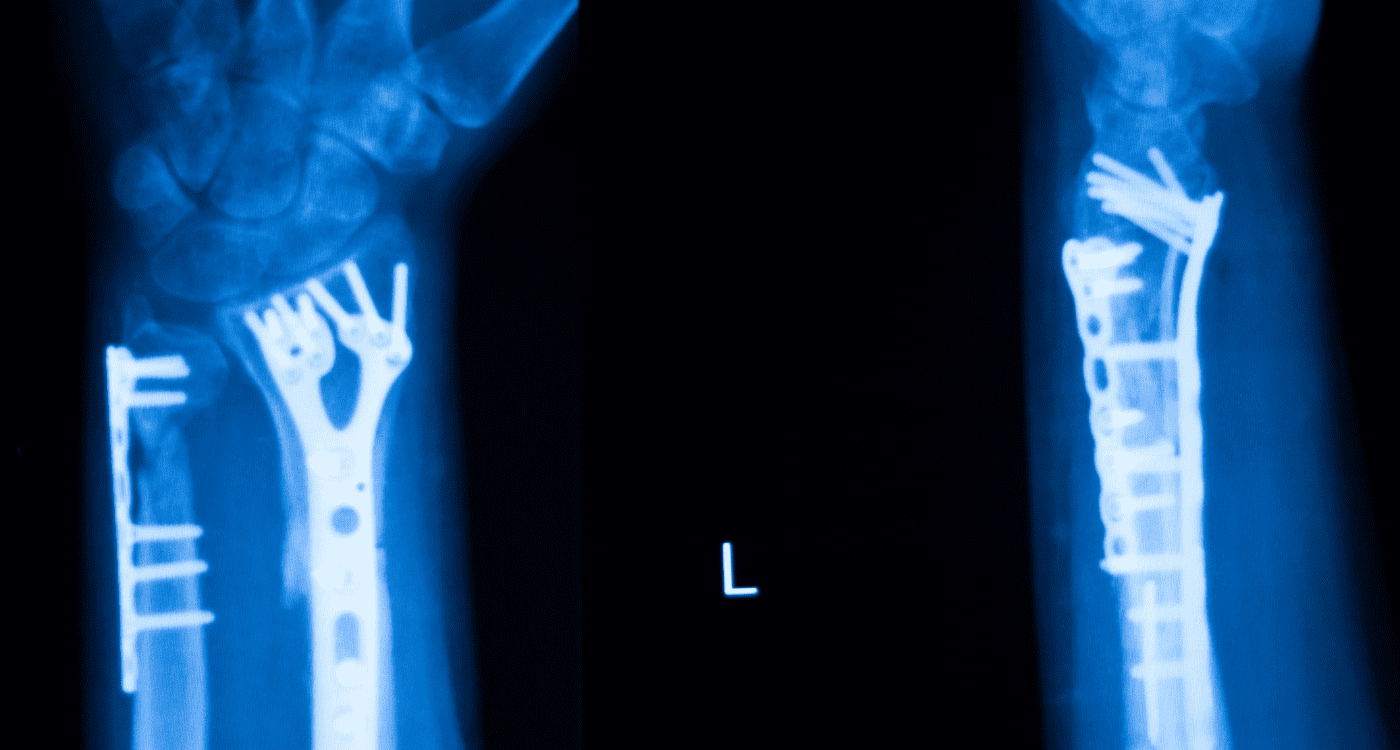

Compromiso articular y lesiones deportivas